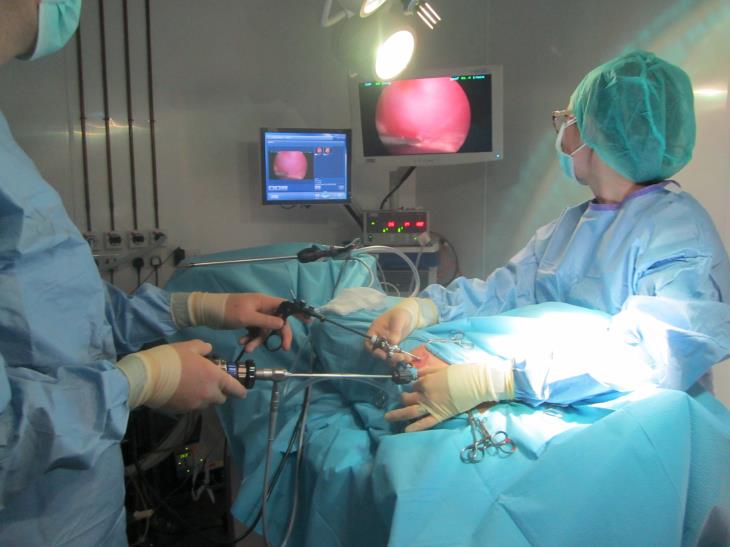

MIS is also becoming increasingly popular among veterinary surgeons. The principles of MIS are that it provides a highly magnified, well-lit image of a region of anatomy that would otherwise require a significantly larger incision and higher morbidity for the equivalent procedure to be performed as an “open surgery”. This, therefore,

MIS is also becoming increasingly popular among veterinary surgeons. The principles of MIS are that it provides a highly magnified, well-lit image of a region of anatomy that would otherwise require a significantly larger incision and higher morbidity for the equivalent procedure to be performed as an “open surgery”. This, therefore,

allows the MIS patients to recover faster and experience less postoperative pain than those animals who undergo equivalent open surgery. There are also significant advantages to the surgeon in that it is often easier to access certain areas of anatomy using MIS, procedures are often faster than the equivalent open surgery and anatomy is greatly magnified potentially leading to an increased sensitivity in detecting early disease.

- We are one of a very small number of centres in the UK with well over 10 years experience in performing MIS procedures. We have accumulated a wealth of experience during that time.

- Eastcott Referrals has invested in top of the range HD systems and advanced instrumentation allowing us to safely perform advanced, complex procedures such as cholecystectomy and thoracic duct ligations.